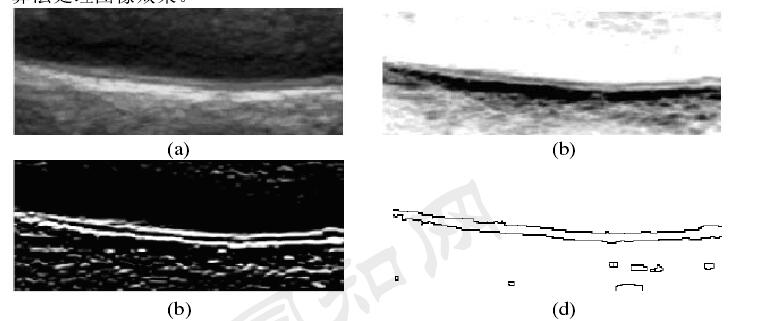

最近看到一篇硕士论文中所研究的内容,在算法上我想想用opencv来实现,故意记录一下。论文名称《基于彩色超声图像的血管内膜中层厚度测量算法的研究》,下面所述的内容部分都是摘要其中的内容。

图1 血管内膜中层原图

图2 整个算法思路